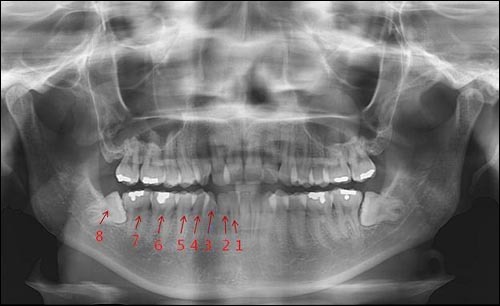

치과치료 고통 사랑니 발치 vs 신경치료

2222222222222222 돌출신경이라서 신경4개 어쩔수없이 죽였는데 진짜 너무 아팠어여ㅠㅠㅠㅠㅠㅠㅠㅠㅜㅜ

둘다 해봤지만 수평매복니가 훨씬 아픕니다ㅎㅎ

임플란트 교정 신경치료 사랑니.. 온갖 치료를 다 했는데 아픈건 매복사랑니가 짱입니다